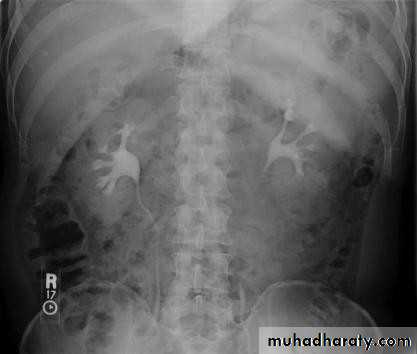

• Intravenous (Excretory) Urography

• Release

• Post -micturation

• Check the Kidneys: outline, size, site

• Check the calyces: cupped• Check renal pelvis and ureter

• Check the bladder